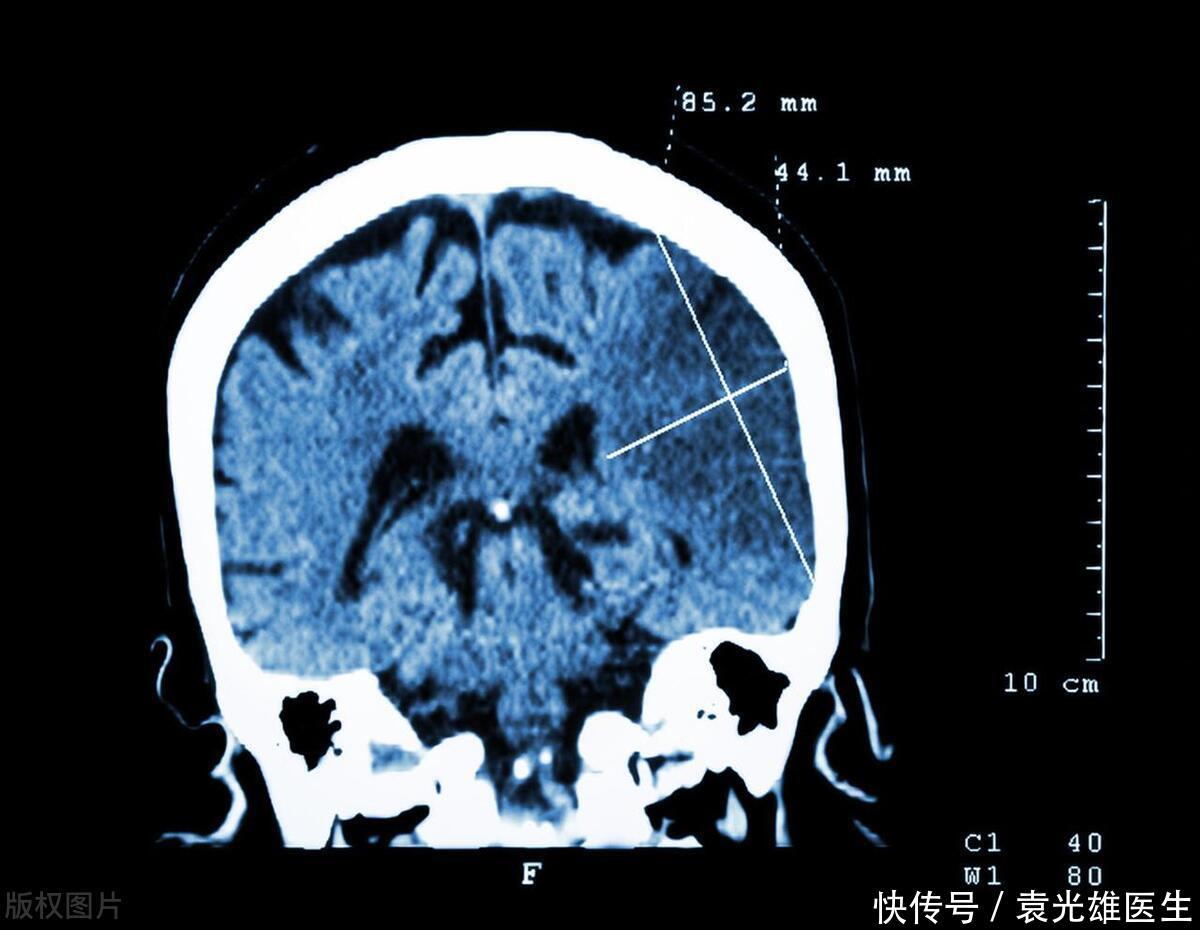

?在现代社会中,脑梗塞已成为威胁人类健康的重大疾病之一。脑梗塞,通常称为“中风”,是由于脑部血管阻塞或破裂导致脑组织损伤,进而影响身体功能。虽然脑梗塞的成因复杂,涉及遗传、环境、生活方式等多个因素,但越来越多的证据表明,不健康的饮食习惯是导致脑梗塞的主要可控因素之一。特别是,某些类型的早餐,因其高盐、高脂、高糖和高热量的特性,被认为是血管堵塞的“帮凶”。本文将探讨四种可能增加脑梗塞风险的早餐食物,并提供健康的饮食建议。